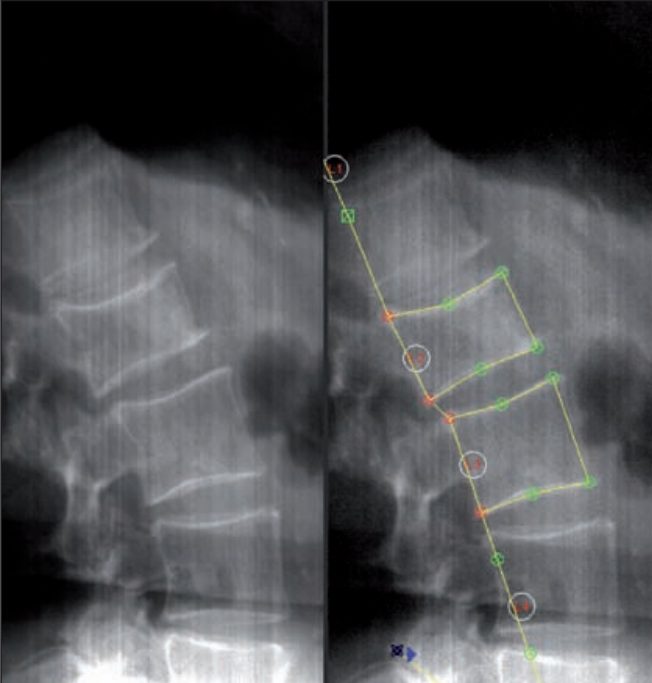

L’analisi morfometrica quantitativa si basa sulla misurazione di tre altezze fondamentali per ogni corpo vertebrale, solitamente nel tratto compreso tra la quarta vertebra toracica (T4) e la quarta vertebra lombare (L4):

- l’altezza anteriore (Ha);

- l’altezza media o centrale (Hm);

- l’altezza posteriore (Hp).

Il radiologo o l’operatore specializzato esamina le vertebre da T4 a L4 e assegna a ciascuna un punteggio di gravità basato sulla riduzione percentuale dell’altezza vertebrale rispetto all’altezza di riferimento (solitamente l’altezza posteriore della stessa vertebra o l’altezza di una vertebra adiacente sana).

La misurazione quantitativa computerizzata automatizza questo processo posizionando sei punti (reperi) su ogni corpo vertebrale, calcolando istantaneamente i rapporti tra le altezze anteriore, centrale e posteriore.